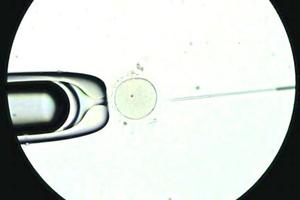

Nace la primera guagua con técnica que activa los espermatozoides